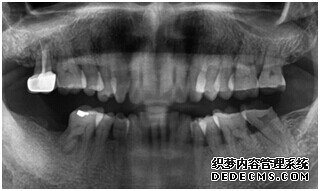

由CT片检查来看,刘女士口腔健康环境还是很好的,牙槽骨也适合种植牙的条件,而且由我们最后一颗牙是非常重要的,经过专家的建议和详细解释了原因之后,刘女士选择了美国百康种植牙。

种植设备检查牙齿

成功植入种植体后的效果图

种植体成功植入后的CT效果图